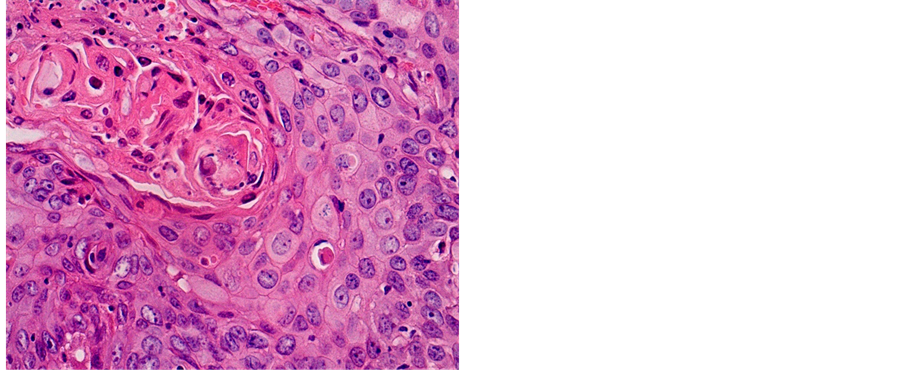

Table 2 shows the distribution of histological types of cancers diagnosed during the study. A total of 1687 (81.18%) cases of squamous cell carcinoma (SCC) and 269 (12.95%) cases of adenocarcinoma (ADK) have been identified (Figures 3-5).

Figure 3. Well differentiated SCC (a) 400×; (b) 200×.